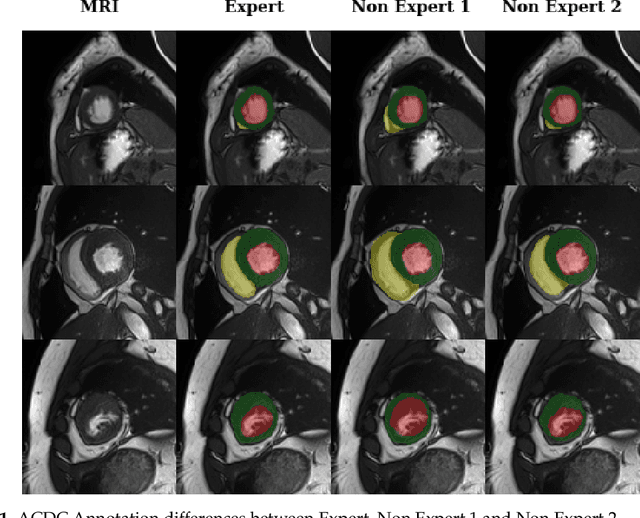

Abstract:Deep learning methods are the de-facto solutions to a multitude of medical image analysis tasks. Cardiac MRI segmentation is one such application which, like many others, requires a large number of annotated data so a trained network can generalize well. Unfortunately, the process of having a large number of manually curated images by medical experts is both slow and utterly expensive. In this paper, we set out to explore whether expert knowledge is a strict requirement for the creation of annotated datasets that machine learning can successfully train on. To do so, we gauged the performance of three segmentation models, namely U-Net, Attention U-Net, and ENet, trained with different loss functions on expert and non-expert groundtruth for cardiac cine-MRI segmentation. Evaluation was done with classic segmentation metrics (Dice index and Hausdorff distance) as well as clinical measurements, such as the ventricular ejection fractions and the myocardial mass. Results reveal that generalization performances of a segmentation neural network trained on non-expert groundtruth data is, to all practical purposes, as good as on expert groundtruth data, in particular when the non-expert gets a decent level of training, highlighting an opportunity for the efficient and cheap creation of annotations for cardiac datasets.